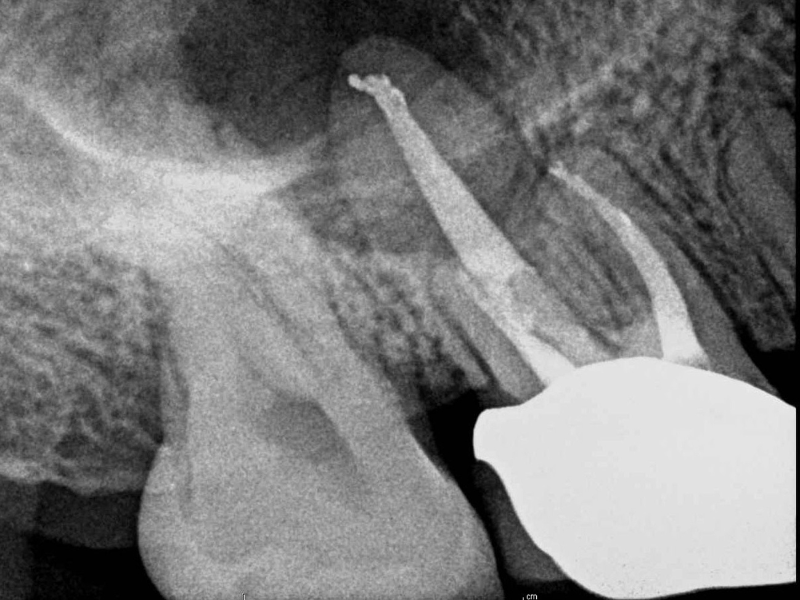

A root canal is a treatment that is used to repair and save a tooth that is badly decayed or that becomes infected. The nerve of the tooth becomes infected or the pulp becomes damaged, and the nerve and pulp is removed and the inside of the tooth is cleaned and sealed. Dental Pulp is the soft area in the center of the tooth where the tooth’s nerve lies. These root canals travel from the tip of the tooth’s root into the pulp chamber, where blood vessels and connective tissue can also be found that nourish the tooth.

When nerve tissue or pulp is damaged it begins to break down, bacteria will begin to multiply within the pulp chamber, and the pulp will need to be removed. The bacteria and other decayed debris can cause an infection or abscessed tooth, and infect the root canal of a tooth.